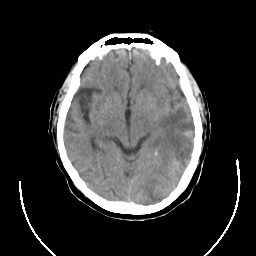

CT Study #3 -- Slice #12